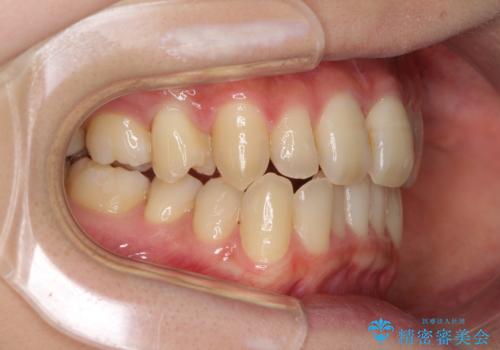

奥歯の反対咬合 上顎骨を拡大してインビザラインで矯正

- 奥歯の反対咬合を気にして来院された患者様です。

反対咬合は上顎骨の幅が下顎骨よりも小さいことが原因なので、拡大装置により骨幅を広げて上下関係を改善し、その後インビザラインにて歯並びを整えることとしました。

反対咬合が改善され、食いしばり癖もなくなり、顎関節の負担が軽減されました。

上顎骨を拡大したことで前歯に隙間ができ、1ヶ月ほど恥ずかしい時期がありましたが、しっかりとした咬み合わせに仕上がり、患者様には大変満足していただきました。